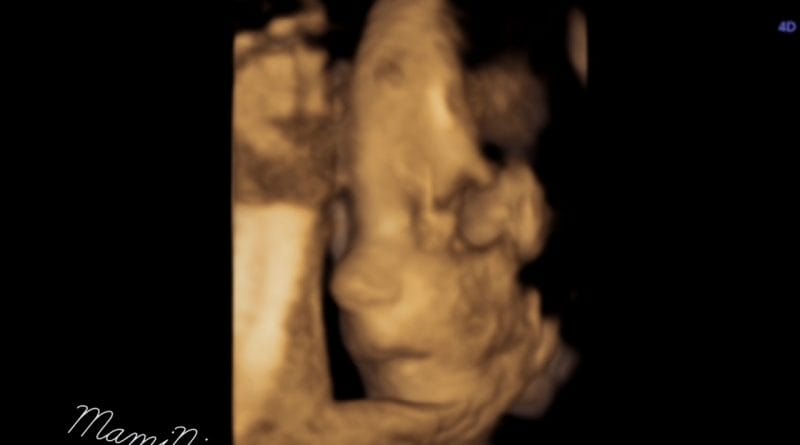

Nosečniški dnevnik 2: 3D/4D ultrazvok

Nosečniški dnevnik 2: 3D/4D ultrazvok v 27. tednu

30. 3. 201730. 3. 2017 zastarse 0 Komentarjev

Končno je prišel težko pričakovani 29. marec, ko smo imeli datum za ultrazvočni pregled v zdravstvenem centru Dravlje. Tega sem